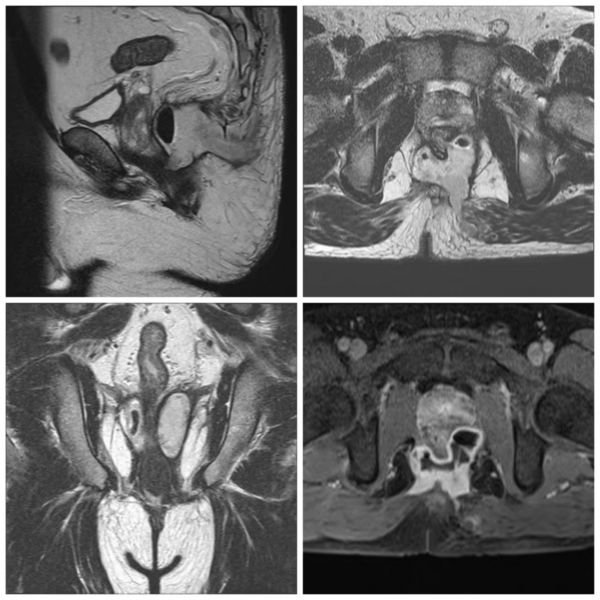

手术现场 6月25日,征得患者及家属同意后,在科主任王定树的指导下,由副主任医师李享祥主刀,主治医师蒋文君等协助,完成了第一期手术,即采用改良Hanley术+松挂线引流术。术后无排便失禁,经过3个多月伤口换药及精心护理,患者肛周痛感已明显缓解,肛周对口引流切口愈合,肛周正后方留置导尿管引流处引流通畅,复查肛管M R I脓腔较前明显缩小,已由“蝴蝶形”脓肿转化为“马蹄形”脓肿。

第二期手术前肛管MRI图